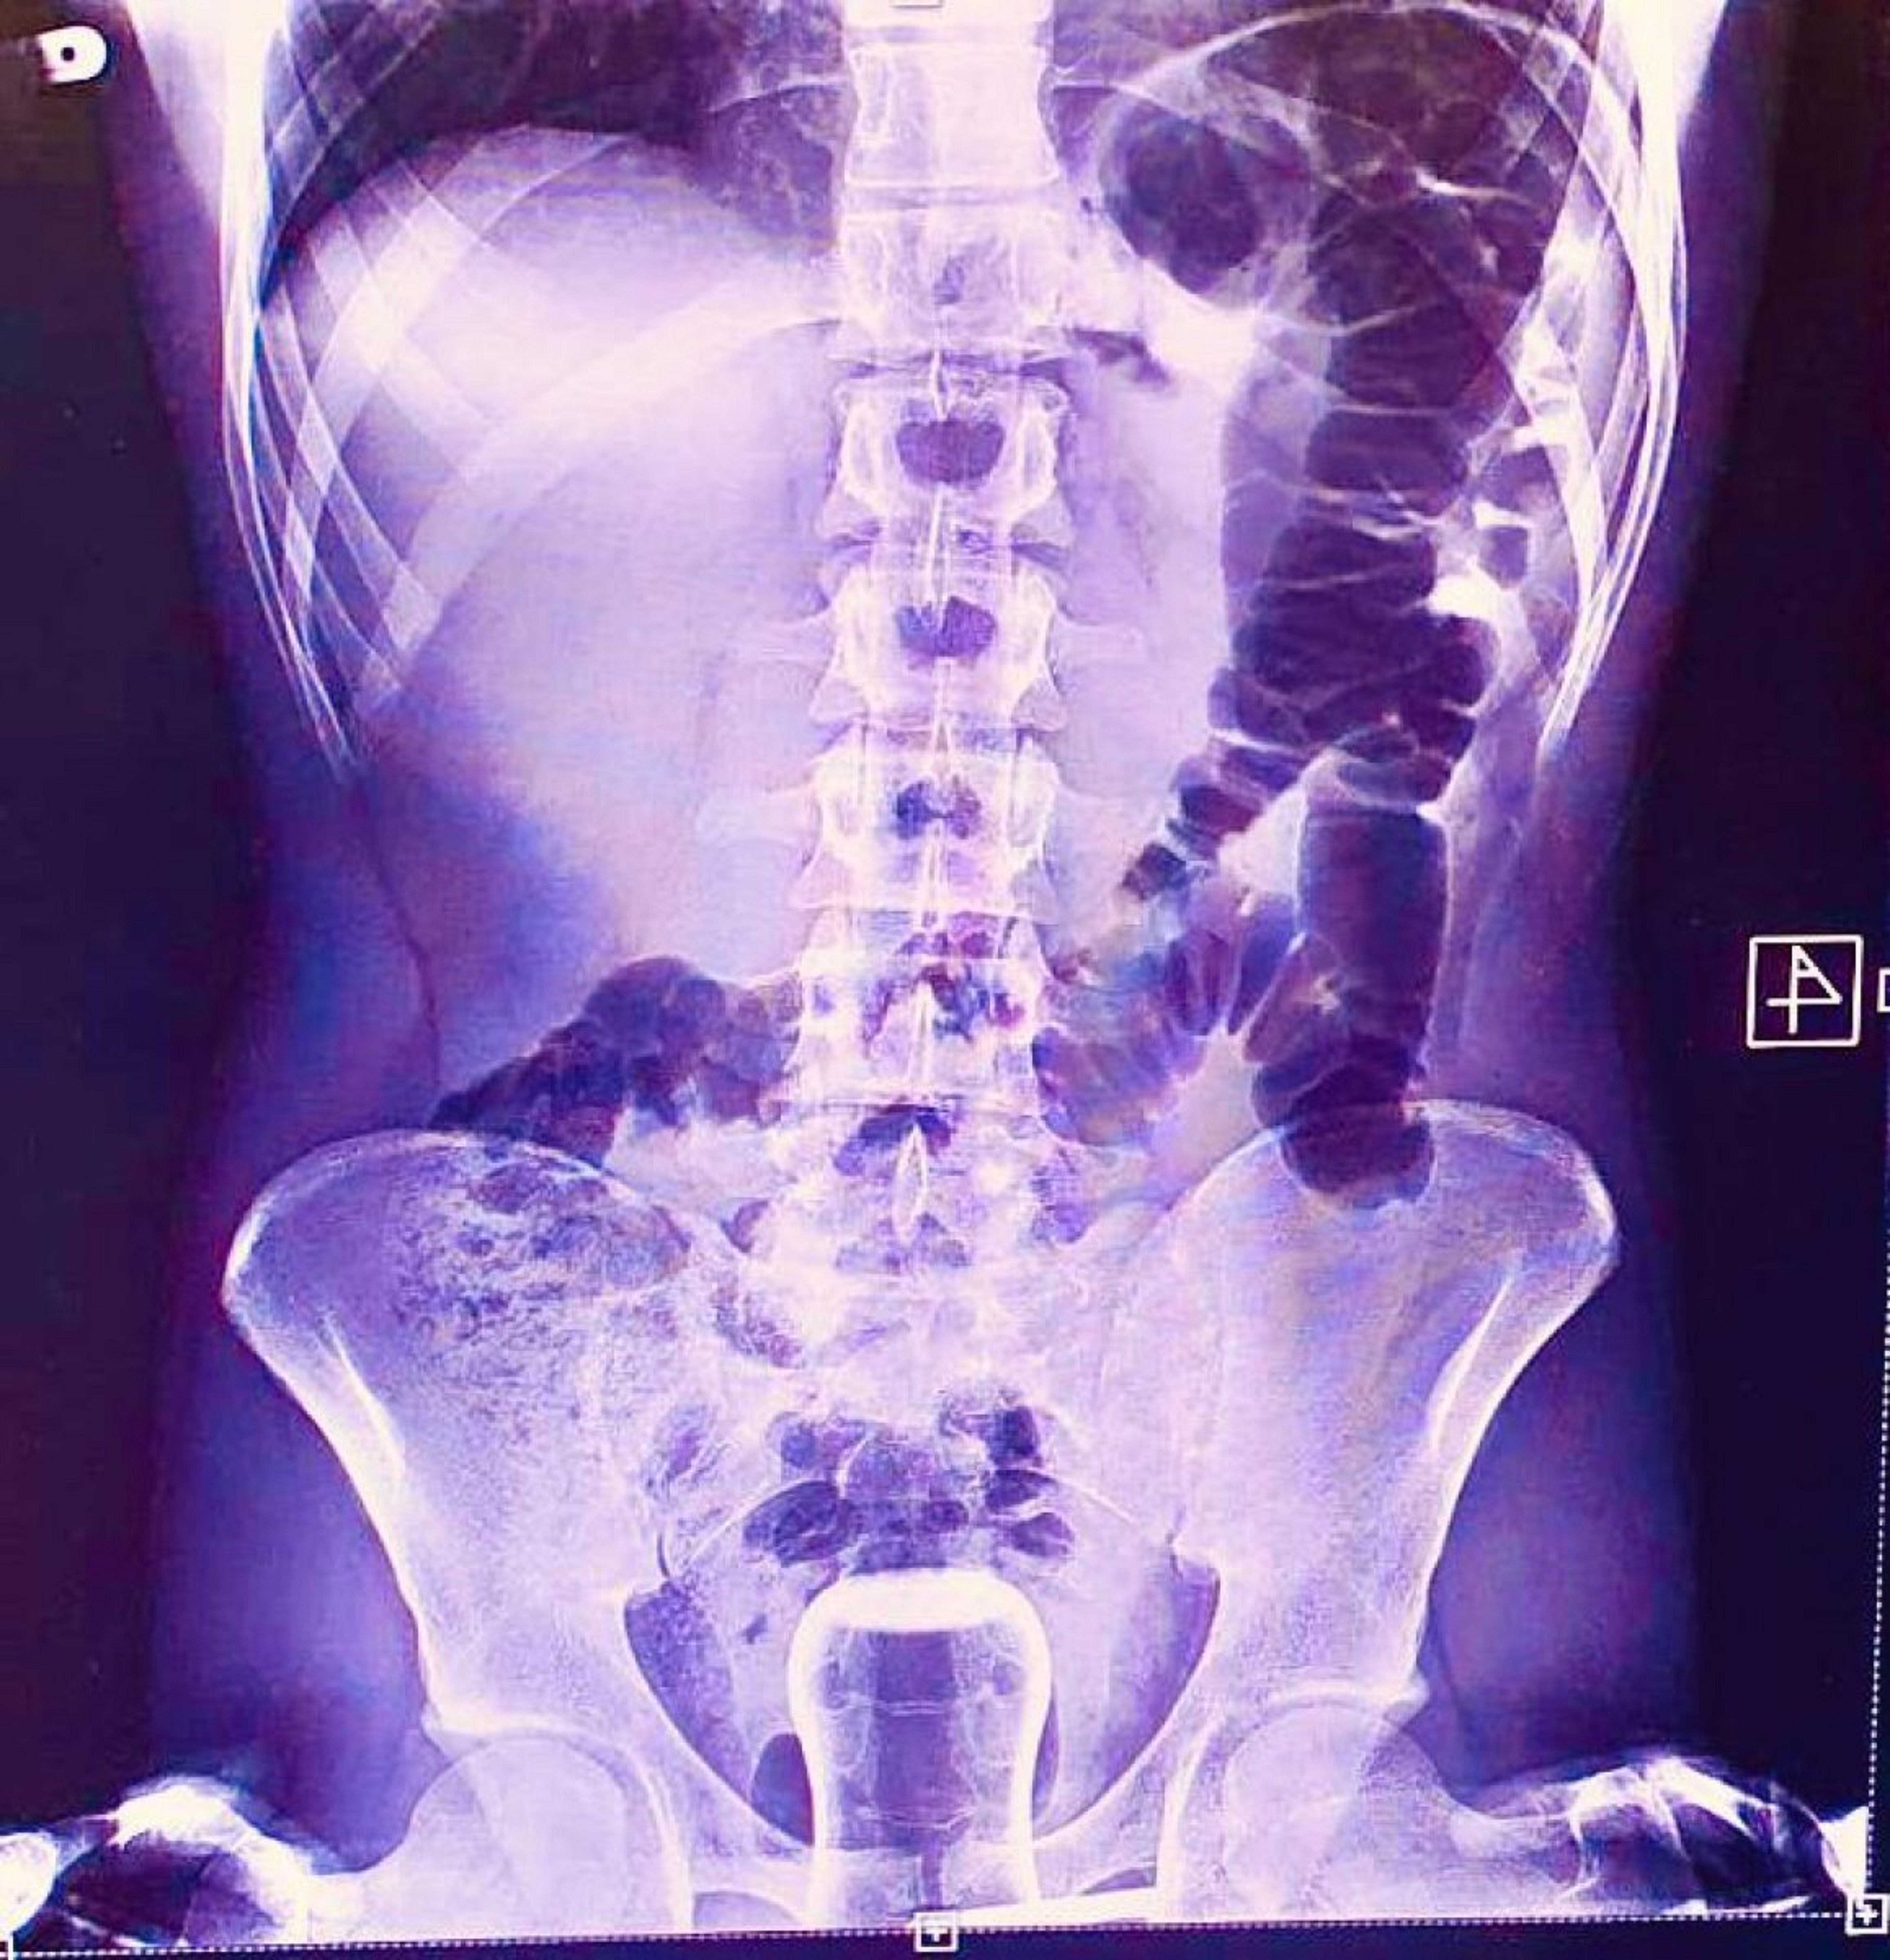

Mehmet Akif İnan Eğitim ve Araştırma Hastanesine başvuran kişi ilk olarak röntgene alındı. Anüs bölgesinde çay bardağının görülmesi üzerine ismi açıklanmayan şahıs ameliyata alındı. Çay bardağı, uzman doktorlar tarafından gerçekleştirilen operasyonla çıkarıldı. Hasta ameliyat sonrasında sağlığına kavuşurken, doktorlar kişinin basur hastası olduğunu ifade etti. Uzun zamandır basur sorunu yaşayan kişi hacamat sırasında anüs bölgesine giren bardaktan kurtulması sonrası doktorlara teşekkür etti.